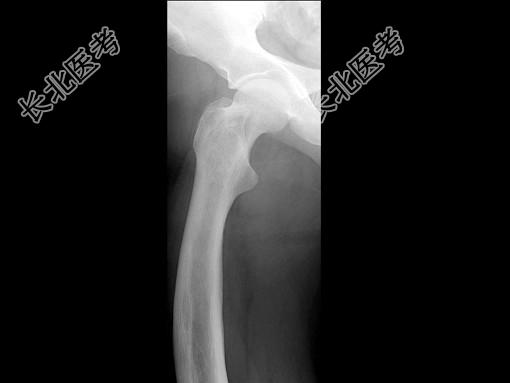

单项选择题男,67岁, 右侧股骨痛,结合图像, 最可能的诊断是 ( )

A、骨纤维结构不良

B、维生素D缺乏病

C、成骨不全

D、软骨发育不全

E、畸形性骨炎